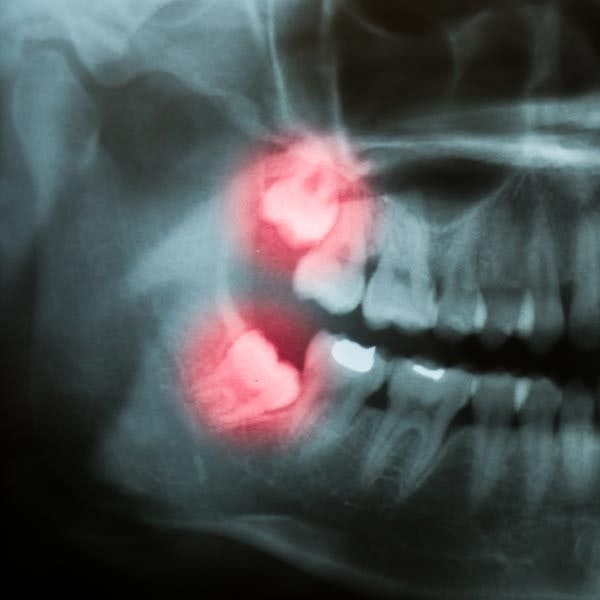

Digital X-Rays:

Digital radiography is a type of imaging that uses far less radiation than traditional x-rays. It also allows us to produce enhanced images of your teeth and other oral structures instantaneously on the computer. Digital x-rays are useful in many types of surgery.